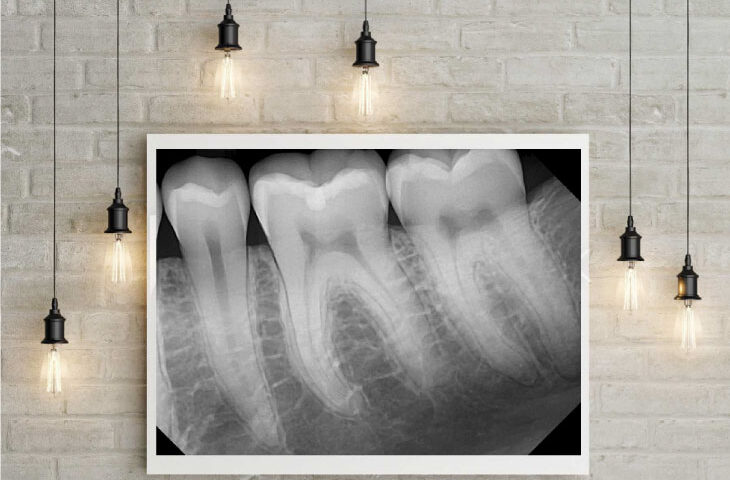

Ramey took an X-ray of Arnett and a few seconds later, Christensen, a renowned prosthodontist, exclaimed, "Nice image!" according to Ramey. The group of experts stood up from their seats and gathered around Christensen, eager to examine the image on his laptop. Ramey recalls this moment with great pride.

"Over time, this secret sauce that he came up with, just the right exposure rates, the right settings, the filters, the software, and just the right combination, he was able to produce these beautiful images," Arnett said.

"I did a lot of work getting the image looking just right, which is kind of art. I do see it as an art form, more than something technical," Ramey said.

Just as people used to turn the radio dial to hear the music without any static or noise on analog radios, Ramey said he "dials in" the image that they capture with DentiMax sensors by finding the optimal exposure settings on the X-ray heads to get the best raw image possible. Then he applies the best filters, enhancements, and algorithms to get the perfect image according to each doctor’s preferences.

"No one else does that," Ramey said. "They have different algorithms in their software that try to optimize the energy that hits the sensor and make the best image they can with it. I do it the opposite way. I find the optimal amount of energy first, get the best raw image I can, and then I make it look good," he added.

"A good-quality image will stay in most patients’ minds and motivate them to schedule needed treatment," Dr. Kent Stapley said. "Not only do patients want a proper diagnosis and early by their dentist, but many of them would also like to see for themselves what is wrong with their teeth."